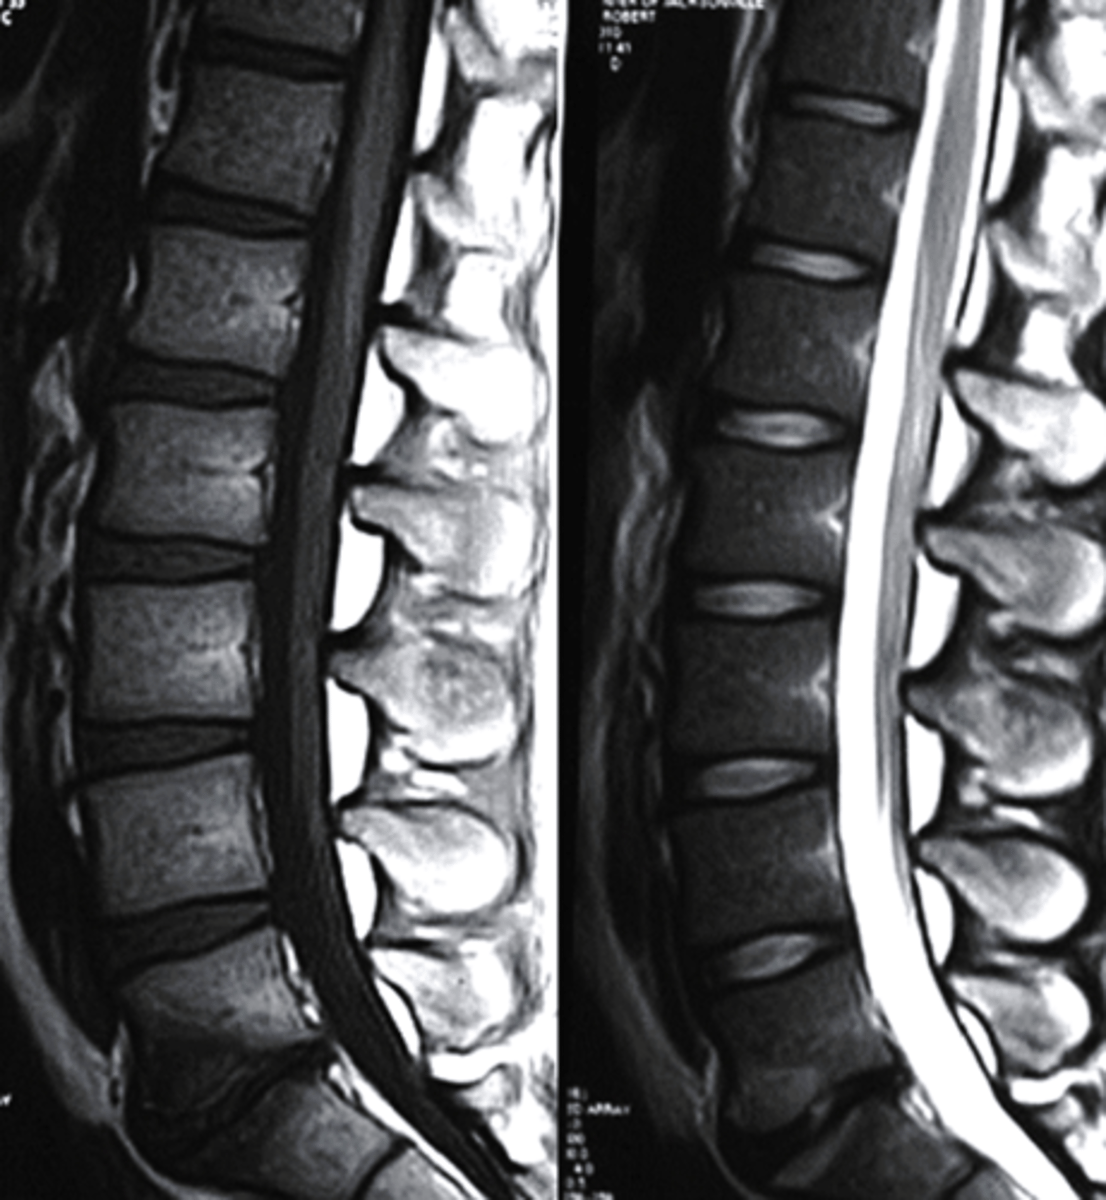

T1 MRI

what type of imaging is this?

a. T2 MRI

b. CT Scan

c. Radiograph

d. T1 MRI

T2 MRI

what type of image is this?

c. T1 MRI

d. conventional radiograph

sagittal

What plane is this MRI?

a. sagittal

b. coronal

c. axial

d. AP